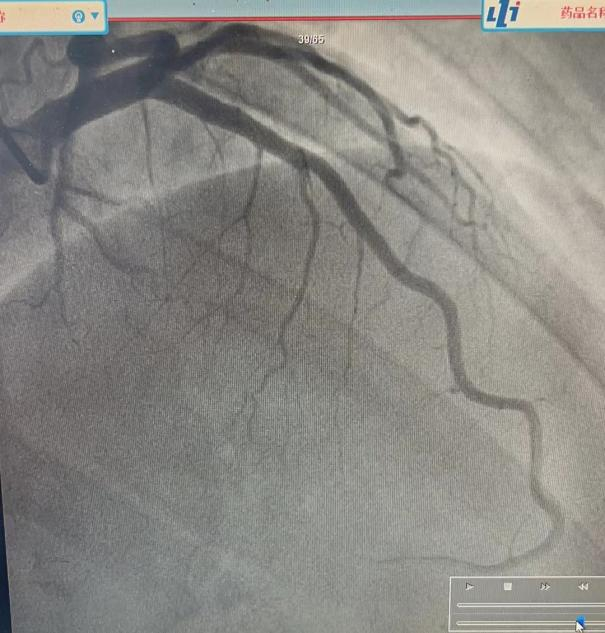

入院后进行了冠脉造影,结果也没有显著狭窄,见图3。

患者自身心绞痛的特点和冠脉造影的结果,坚定了我们对患者是特殊类型心绞痛的信心。进一步追问后,发现患者不但卧位翻身时疼痛加重,而且立位时抬头或屈颈都有可能症状加重。

为了排除真正的心绞痛,必须进行不同程度的心脏检查。传统的方法,如亚硝酸盐反应,休息和负荷心电图,或疼痛的特征,都有相当高的错误率。重要的是,冠状动脉造影的使用使我们能够比过去更经常、更准确地排除心脏病导致的胸壁疼痛[1]